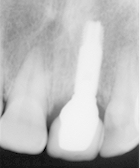

A partir de ce modèle, le laboratoire de prothèse réalise  la dent artificielle qui sera vissée soit directement sur l'implant, soit scellée sur une pièce intermédiaire (inlay-core).

L'inlay core est vissé dans l’implant et la couronne est scellée sur l’inlay core.